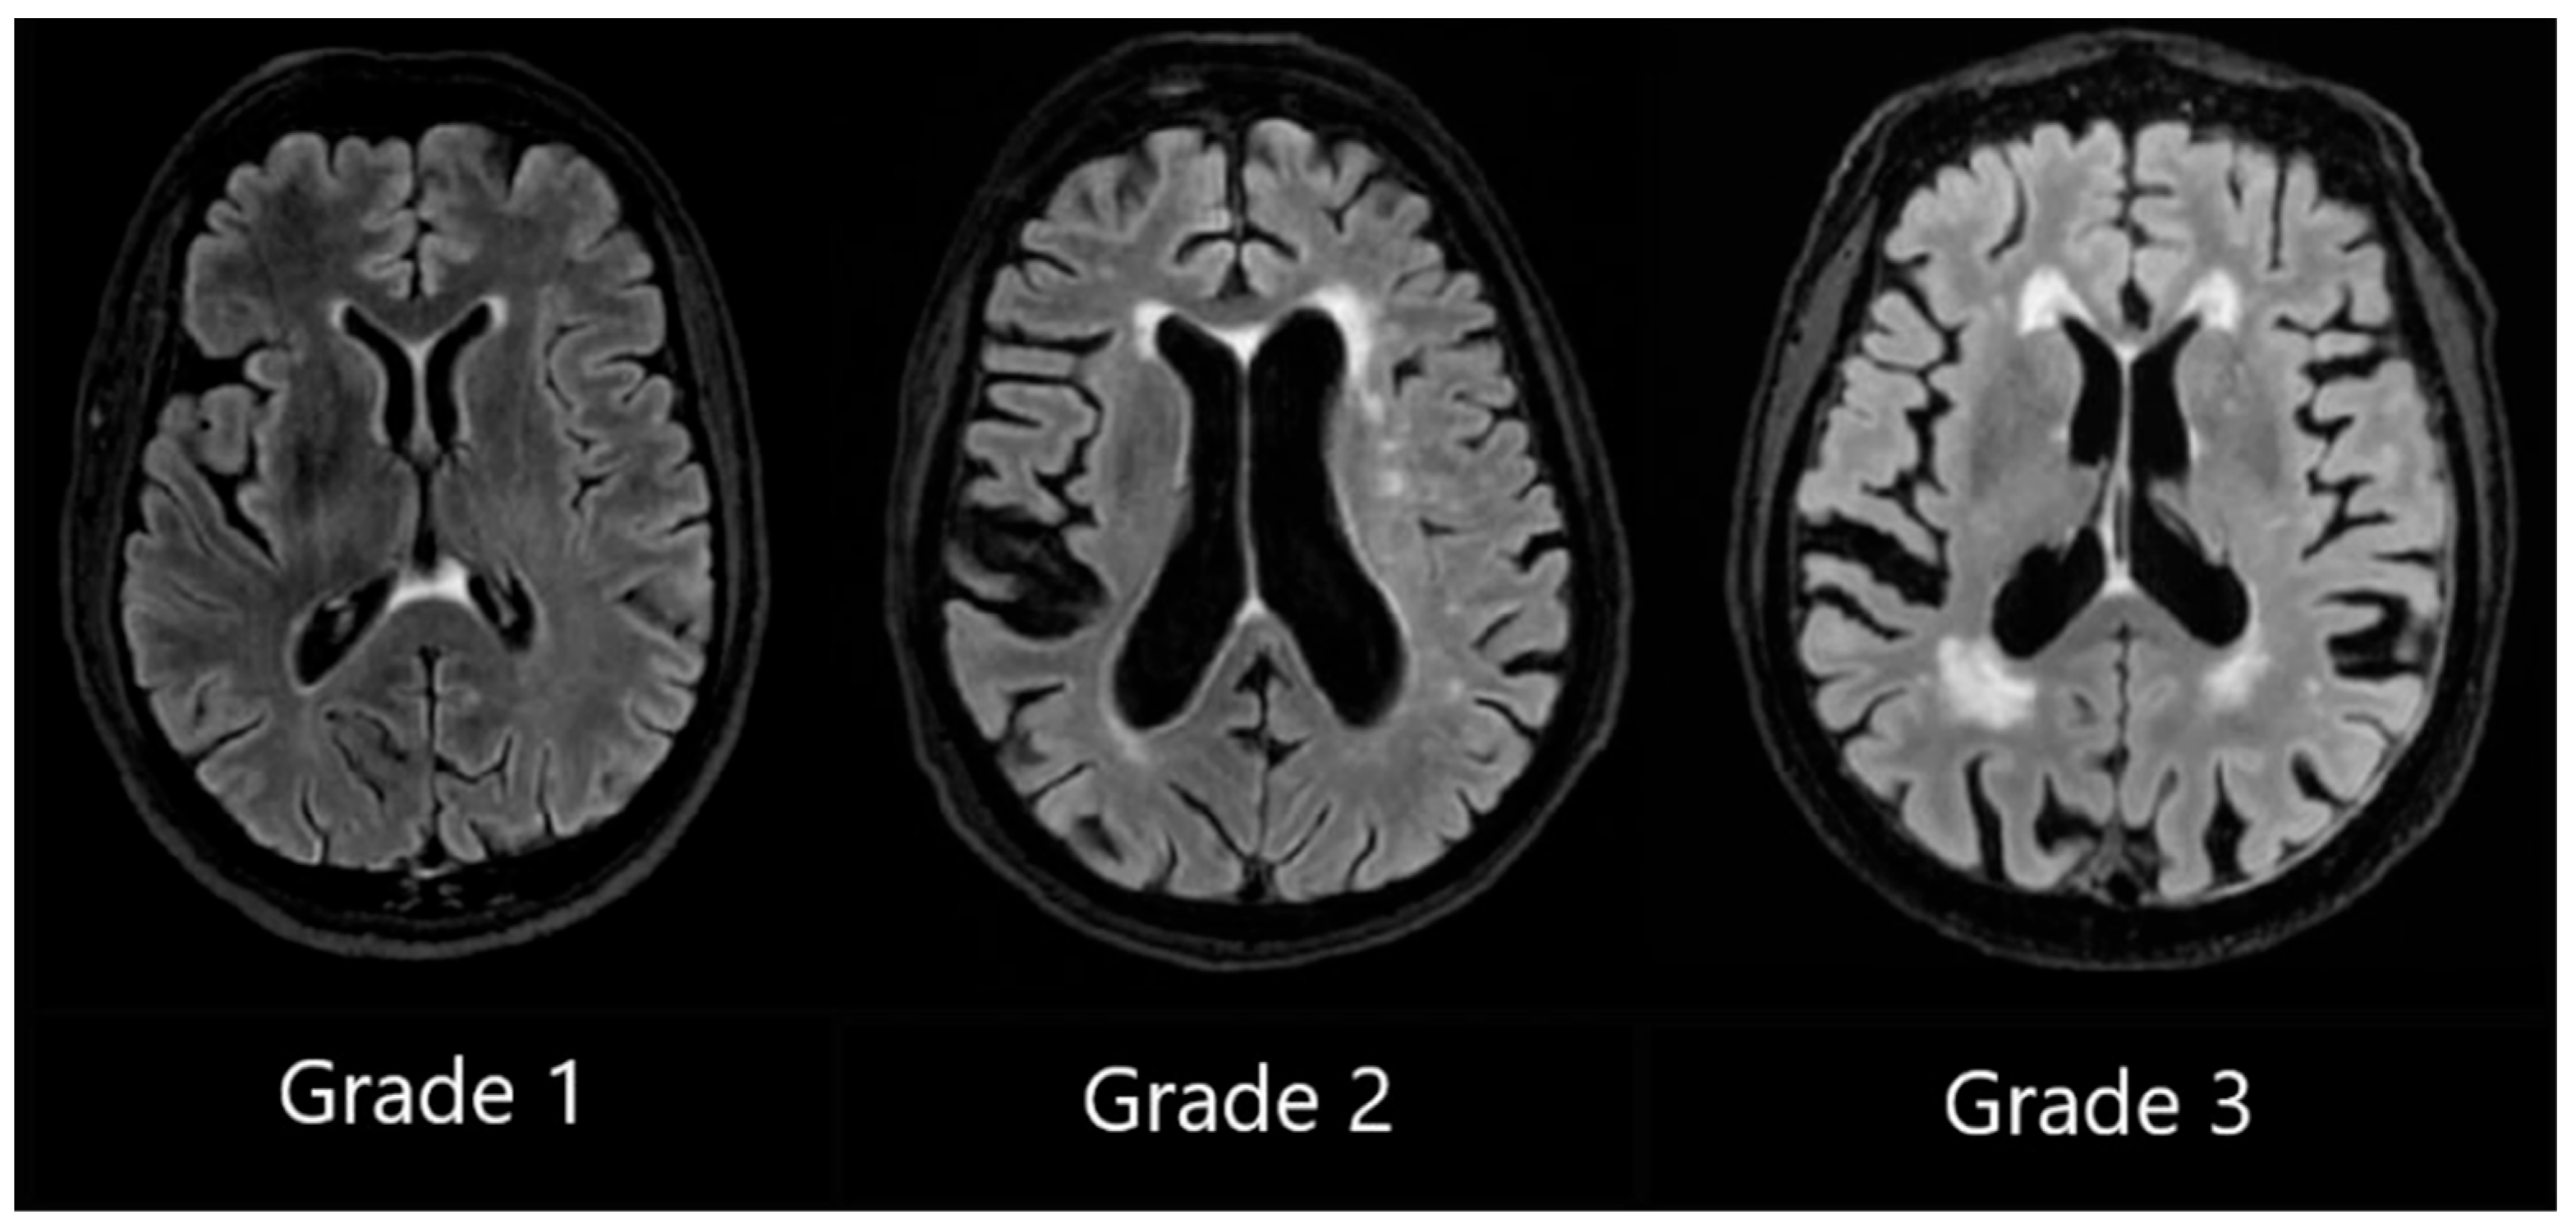

DWMH Grade 1 was assigned when small, punctate foci in subcortical regions were observed, Grade 2 was assigned to patients with a greater number of foci along with the early formation of white matter hyperintensity confluences, and Grade 3 was assigned to patients with large confluent areas of white matter hyperintensities (see Figure 2).

Figure 2. Deep white matter hyperintensities based on the Fazekas scale, ranging from Grade 1 to Grade 3, based on the severity of lesions.